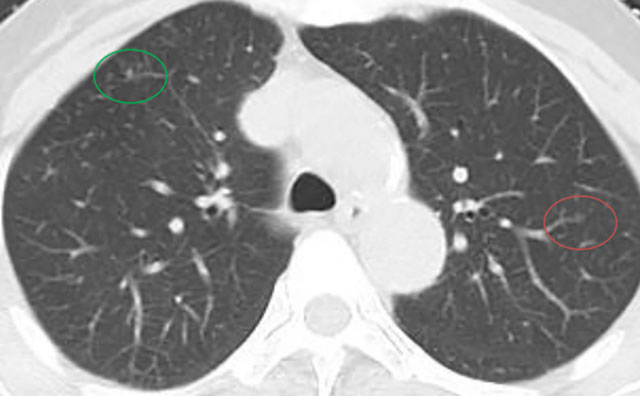

近期,阿姨复查影像展示与分析,1mm层薄层。

与术前及每年复查片对比,阿姨双肺多发磨玻璃结节,均未见显著改变,左肺上叶前段主病灶亦如此,密度很纯,未见增大及实性成分出现,术后5年虽可见血管弯曲,进展极慢,风险还是相对较低,且右肺上叶已经全切除。双肺多发相对较小磨玻璃密度结节,并且进展极慢、仍纯磨密度。该病灶目前没有必须到手术干预程度,只需6-12月复查随访,若有进展并要有风险增加时再考虑干预处理。